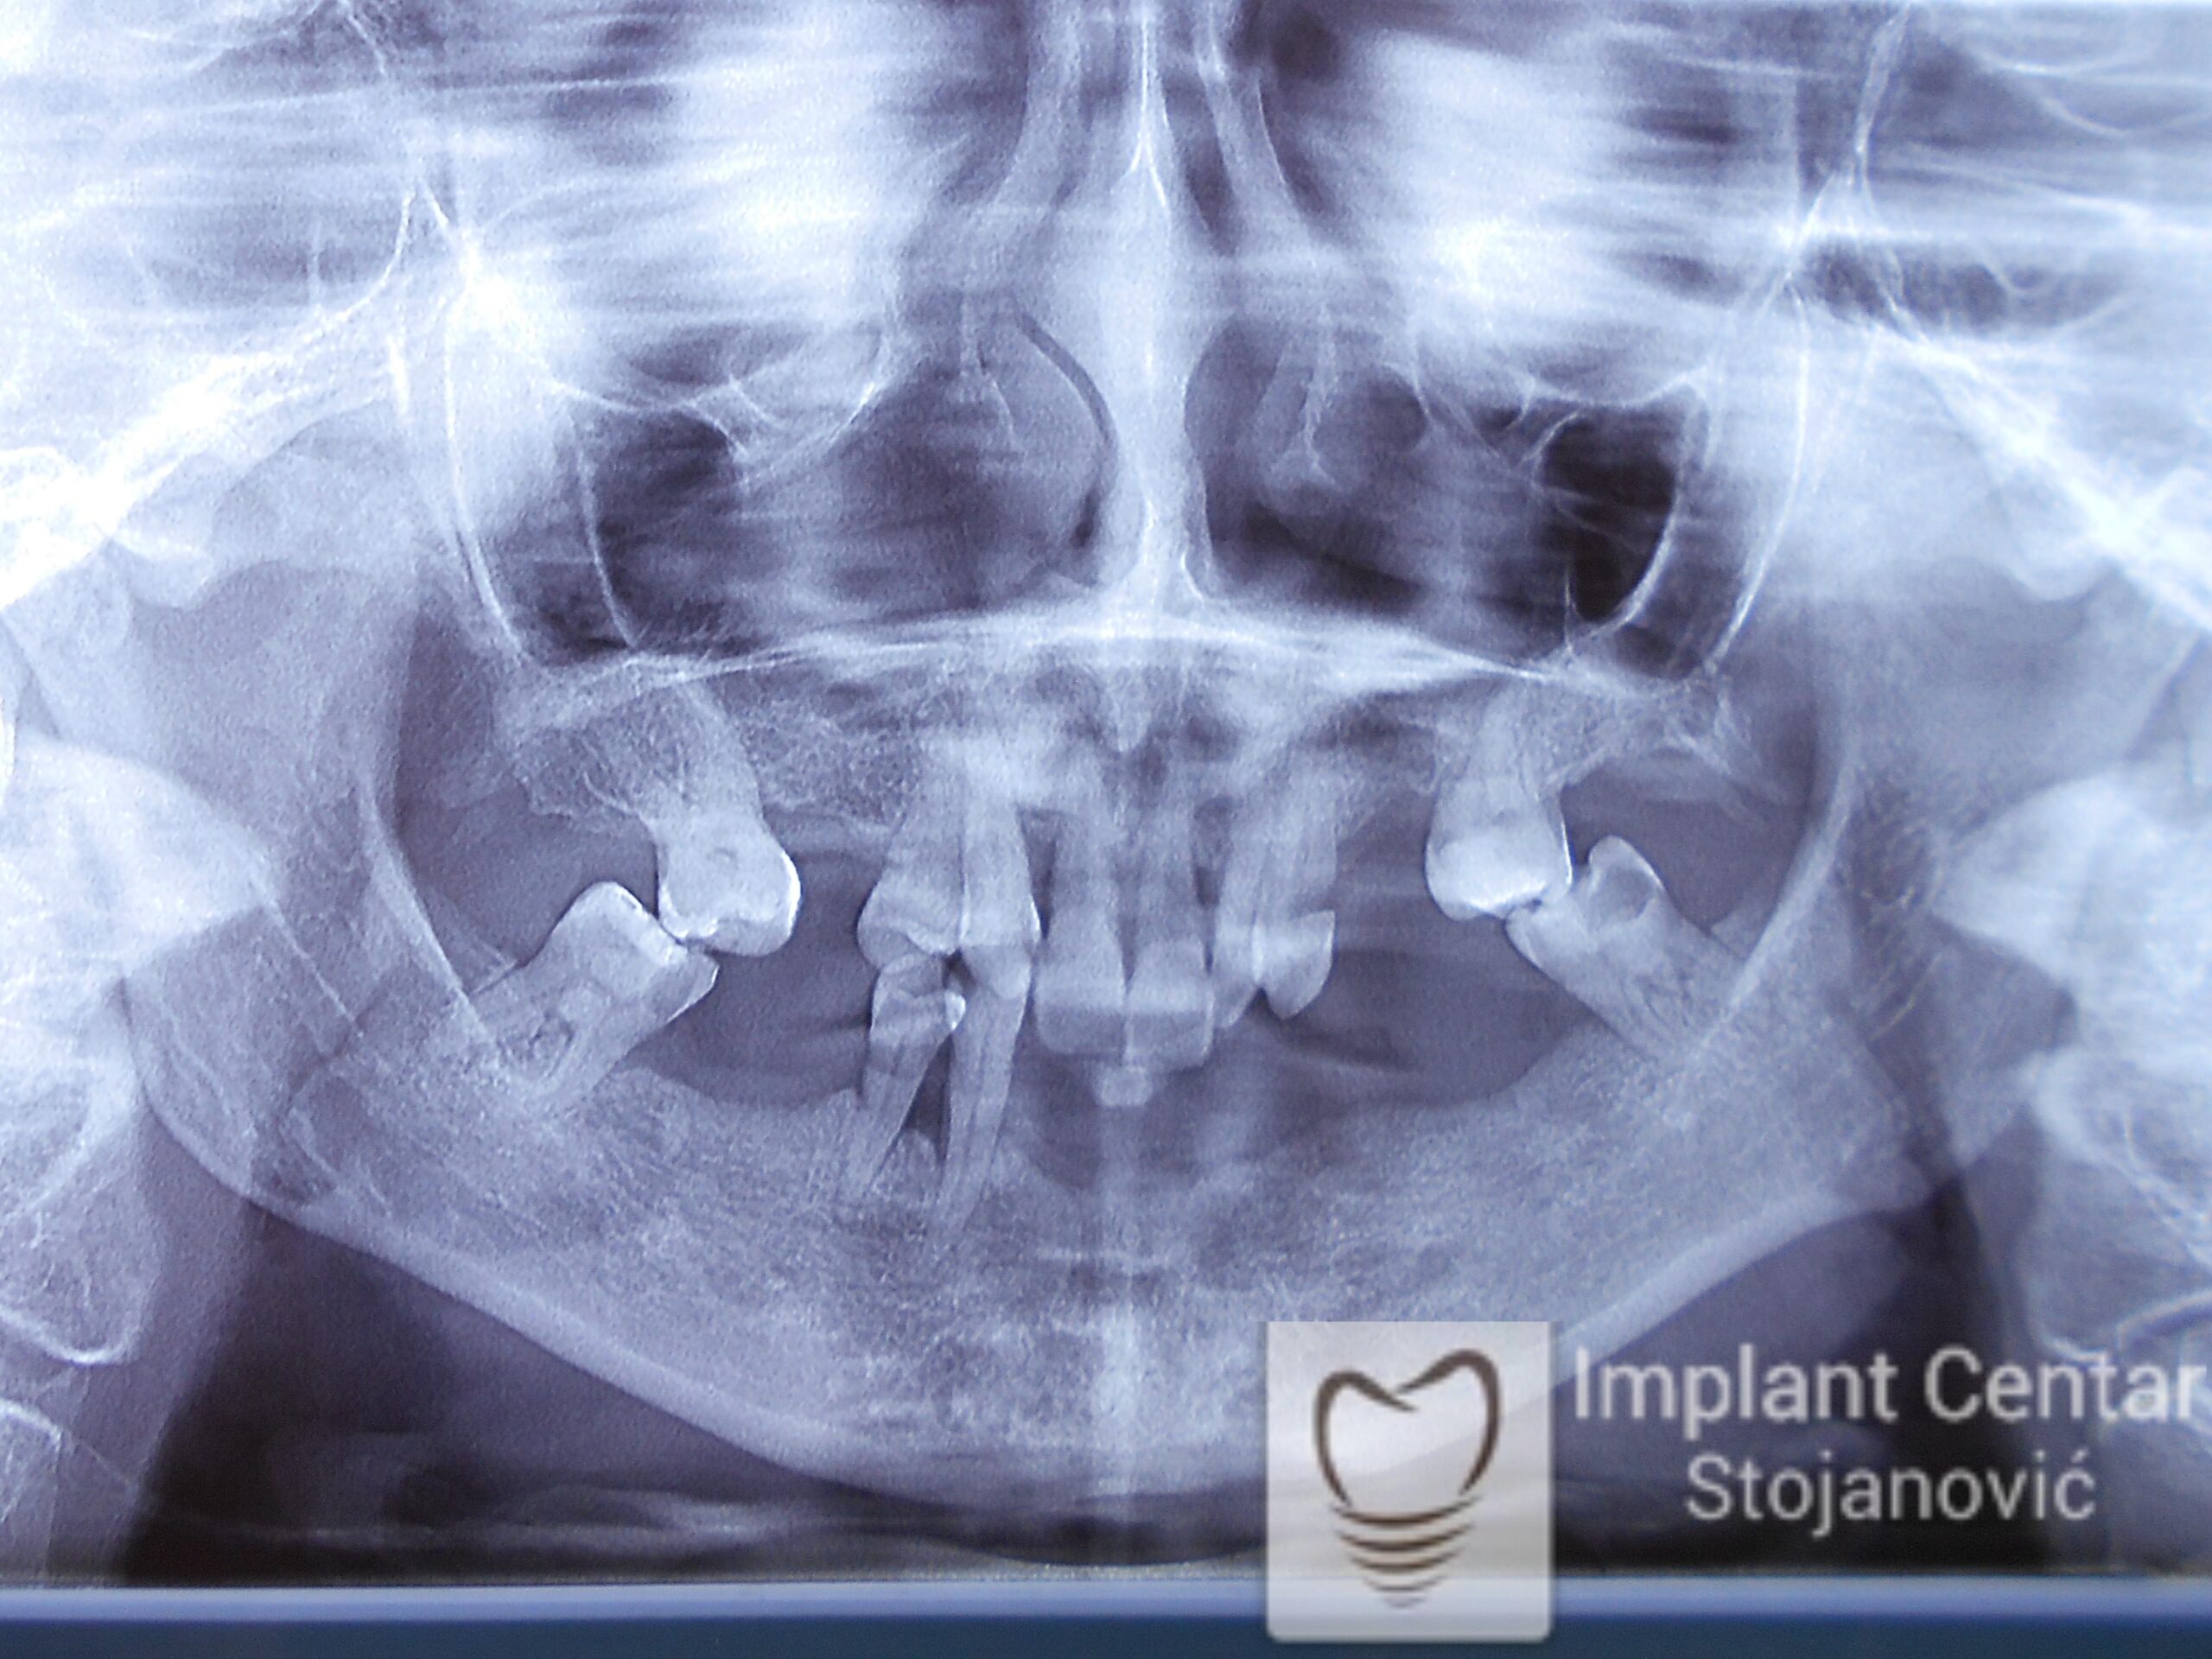

Pacijent kod koga je, zbog uznapredovale parodontopatije, bilo indikovano vađenje svih preostalih zuba.

Na slici 1. i slici 2. prikazan je izgled pacijenta pre početka terapije – klinički i rendgenološki.